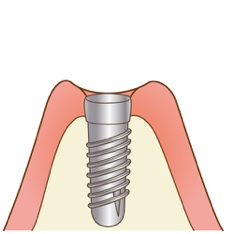

インプラントとは、歯を失ってしまった部分のあごの骨に結合するようにしっかりと埋め込む金属の人工歯根のことを言い、ご自分の歯のように噛むことができます。その上に土台と、最後に人工歯を装着します。

手順1:インプラント体を埋め込みます。

手順2:歯肉を縫合し3~6カ月の安静期間をおきます。